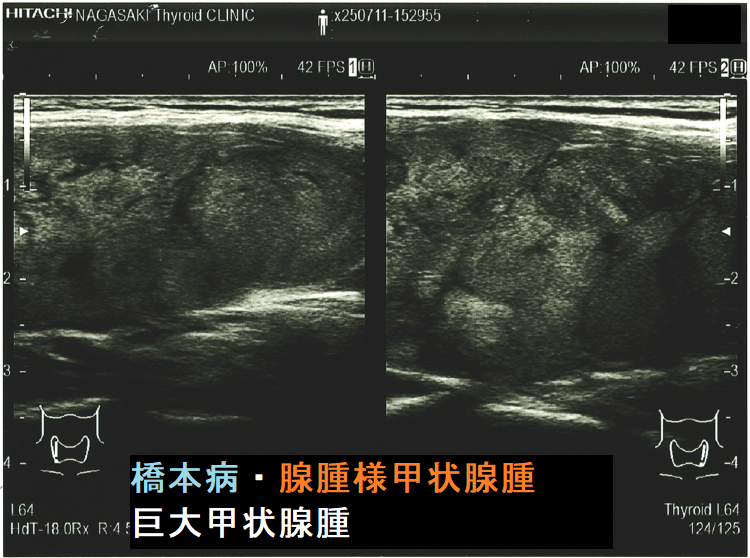

ケース④ 橋本病を基盤とする腺腫様甲状腺腫(気管・食道圧排)

橋本病を基盤とする腺腫様甲状腺腫(気管・食道圧排) 矢状断;等エコーなので甲状腺悪性リンパ腫が隠れているようには見えないが、潜在性甲状腺癌(甲状腺ラテント癌)が存在する可能性は否定できない。かなり気道圧迫している。

ケース⑤ 橋本病を基盤とする腺腫様甲状腺腫・巨大甲状腺腫(気管・食道圧排)